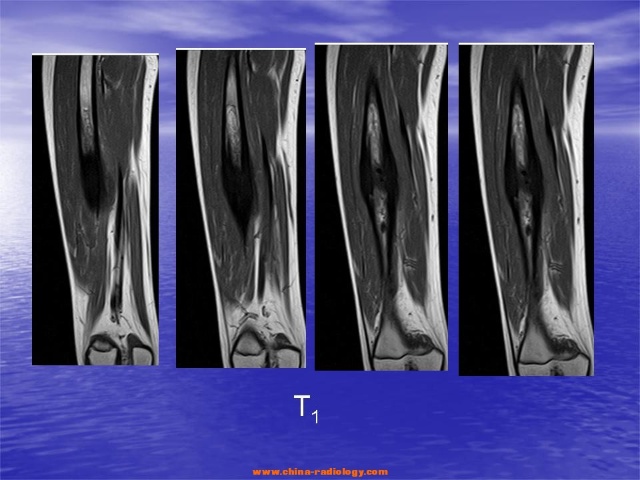

多数认为硬化性骨髓炎是由低毒感染引起、以骨质硬化为主要特征的慢性骨髓炎;由瑞士外科医生Garre于1891年首先报道,又称为慢性非化脓性骨髓炎,其病程缓慢,多侵犯长骨,如股骨、胫腓骨,在老年人中并非少见。

主要是因进行性弥漫性骨干硬化性炎症使骨髓腔内发生广泛性纤维化,引起骨内氧张力及血液供应减少,致骨内膜下新骨形成,骨皮质呈梭形增大,骨髓腔因而变狭窄,甚至消失,骨皮质密度增高,病骨变粗大,与健侧骨对比明显不同。其化脓、骨腔及死骨等慢性骨髓炎的典型病理改变很少出现。>>>将自己的病情描述给医生诊断?